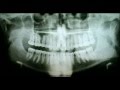

Важно отметить, что временная пломба является временным решением и требует последующего лечения для полного излечения пульпита. Врач стоматолог проведет необходимые процедуры, такие как удаление пораженной пульпы и закрытие каналов зуба постоянной пломбой.

Мед. обработка корневых каналов, пломбирование гуттаперчей и гидроокисью кальция. Лечение.

Лечение периодонтита, второе посещение. Пломбирование каналов зуба.